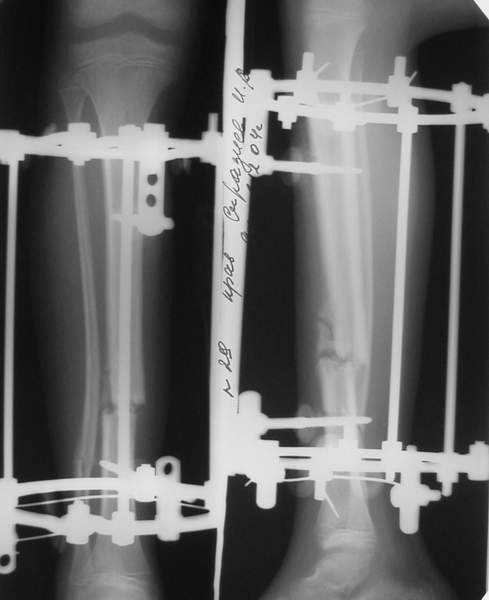

Под рукой прилагаемый пример. Как видите, "стриптиз-аппарат" (шутка проф. З.К.Башурова): 3 кольца-2 кольца-2 полукольца. В случае, который представил Евгений, характер повреждения позволил бы сразу использовать аппарат на основе 2 колец; в крайнем случае прокс. опора м.б. демонтирована сразу после репозиции.

LNS> Под рукой прилагаемый пример. Как видите,

Исходя из него главное преимущество "двух полуколец" - это полный объем сгибания в

коленном суставе, но...

незначительно он отличается от варианта "два кольца"...

В аттачтах №№ 1 и 2 - примеры, когда 2 кольца не позволили послеоперационно

исправить смещение фрагментов большеберцовой (по ширине и вальгусное).

А казалось бы (#2) - поиграй на штангах и все влетит.

1

1a

2

3a

3b

3c

В аттачте № 3 - один из примеров полукольцевого аппарат...